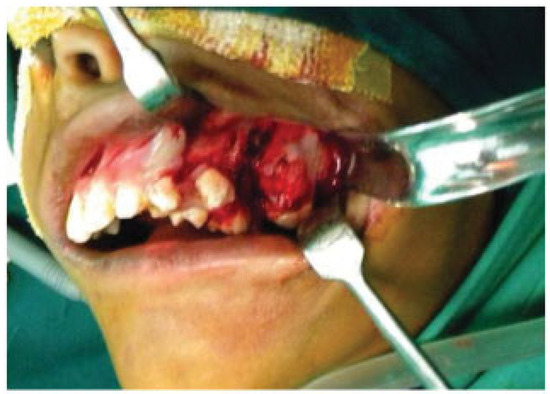

- Incomplete Tessier 7 soft tissue facial cleft and a complete skeletal Tessier 7 cleft on the right side

- Incomplete Tessier 5 skeletal and soft tissue Tessier 6 facial cleft on the left side